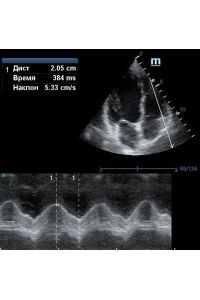

TAPSE - показатель амплитуды движения латеральной части кольца трикуспидального клапана, позволяет количественно и быстро оценить систолическую функцию правого желудочка, норма которого составляет более 17 мм. Главным условием является проведение линии М-режима параллельно стенке правого желудочка в апикальном четырех камерном сечении, что легко достигается при Free Xros.

MAPSE - амплитуда движения латерального кольца митрального клапана, позволяет рассчитать фракцию выброса по формуле EF = 4.8 × MAPSE (mm) + 5.8, очень быстрый и гораздо более точный («прародитель Strain») метод чем широко распространенный метод Teicholtz. В современных приборах можно легко добавить свою формулу при отсутствии ее в стандартном калькуляторе. Главным условием является проведение линии М-режима параллельно стенке левого желудочка в апикальном четырехкамерном сечении, что легко достигается при использовании функции Free Xros.